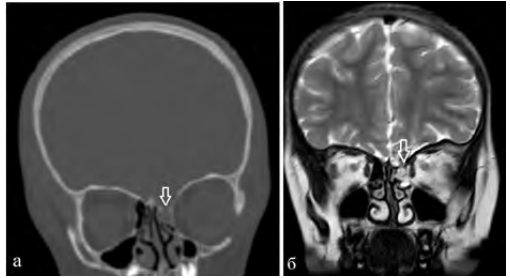

Пациент Н., 5 лет, был направлен в Центр в связи с назальной ликвореей. Из анамнеза известно, что три месяца назад перенес черепно-мозговую травму в результате ДТП. Отмечались ушиб головного мозга тяжелой степени с формированием контузионно-геморрагического очага 2 типа лобной доли, субарахноидального кровоизлияния, множественных дефектов в области лобной пазухи, крыши решетчатого лабиринта слева. По данным КТЦГ выявлялось менингоцеле клеток решетчатого лабиринта, признаки истечения ликвора из дефекта в крыше решетчатого лабиринта (рис. 4).

Рис. 4. КТЦГ фронтальная проекция, менингоцеле клеток решетчатого лабиринта слева. Стрелкой указан дефект в области крыши решетчатого лабиринта

Пациентка Н., 6 лет, обратилась в Центр нейрохирургии с жалобами на периодические жидкие выделения из левой половины носа, нарушения обоняния, головные боли. По данным анамнеза в 5 лет получила травму в результате ДТП. Лечилась по месту жительства с диагнозом: сочетанная автодорожная травма: тяжелая лобно-лицевая травма. Ушиб головного мозга тяжелой степени. Паренхиматозно-субарахноидальное кровоизлияние. Вдавленный перелом лобной кости с переходом линии перелома на верхнеглазничные края орбит, корень носа, чешую височной кости справа, на переднюю черепную ямку. Перелом верхней челюсти справа. Гематосинус справа. По месту жительства проведена операция: декомпрессионная трепанация с удаление вдавленных отломков лобной кости. Спустя месяц пациентка выписана в удовлетворительном состоянии под амбулаторное наблюдение педиатра и невролога. Вскоре отметили появление жидких выделений из полости носа слева. Выполнено КТ, МРТ, на которых выявлено трансэтмоидальное менингоцеле, дефект основания черепа в области крыши решетчатого лабиринта слева (рис. 5).

Рис. 5: а — КТ, б — МРТ, фронтальная проекция, менингоцеле клеток решетчатого лабиринта слева. Стрелкой отмечен дефект крыши решетчатого лабиринта